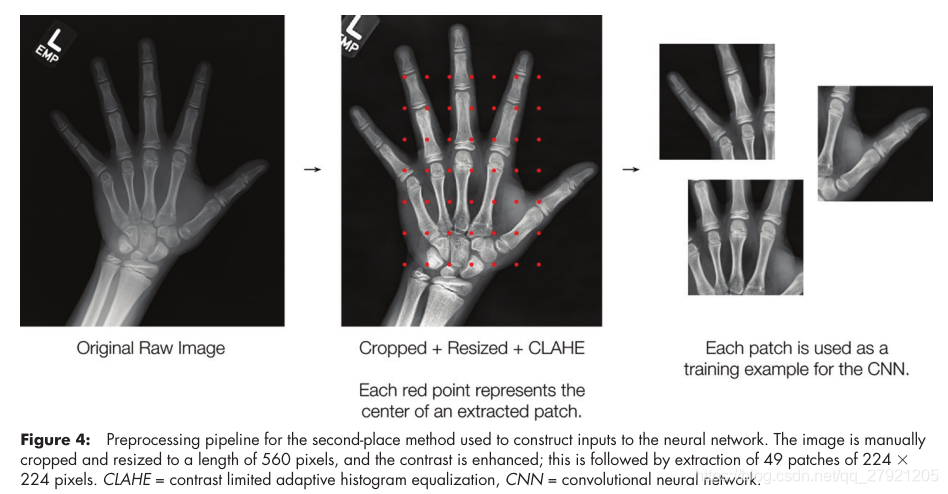

第二名: Ian Pan-MAD=4.350

输入:把原图缩放到560,再切块49份,大小为224X224,对比度增强,男性和女性分开训练

网络:Resnet-50,基于ImageNet的预训练模型